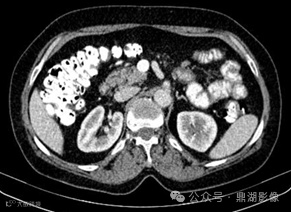

患者,女,55岁,长期腹泻、体重减轻和缺铁性贫血。

口服造影剂后CT平扫

CT小肠造影显示回肠袢轻度扩张,回肠皱襞增多、空肠皱襞减少,并伴有多个肠系膜淋巴结肿大。未发现肠套叠、狭窄或肿块形成等征象。

空回肠皱襞模式反转

空回肠皱襞模式反转(称为回肠空肠化,空肠皱襞减少,回肠皱襞增加)是乳糜泻最特异的征象,文献报道其敏感性和特异性(阳性预测值和阴性预测值)接近100% 。 5cm距离内回肠皱襞数量多于空肠皱襞数量时,则被认为是阳性。

CT和MR小肠造影中,空回肠皱襞模式反转和肠系膜淋巴结肿大是乳糜泻的特征性表现。疾病的严重程度差异极大,从节段性受累到弥漫性小肠受累不等,但最常累及近端空肠。

在CT和MR小肠造影图像上观察到每英寸(=2.54cm)肠段的皱襞少于或等于3个,则认为空肠皱襞密度降低。在重度乳糜泻中,空肠皱襞可能完全消失。在慢性炎症的情况下,回肠皱襞密度可能代偿性增加,定义为每英寸超过5个皱襞,以增加小肠表面积。皱襞数量的增加代表回肠对空肠吸收能力下降的一种适应。